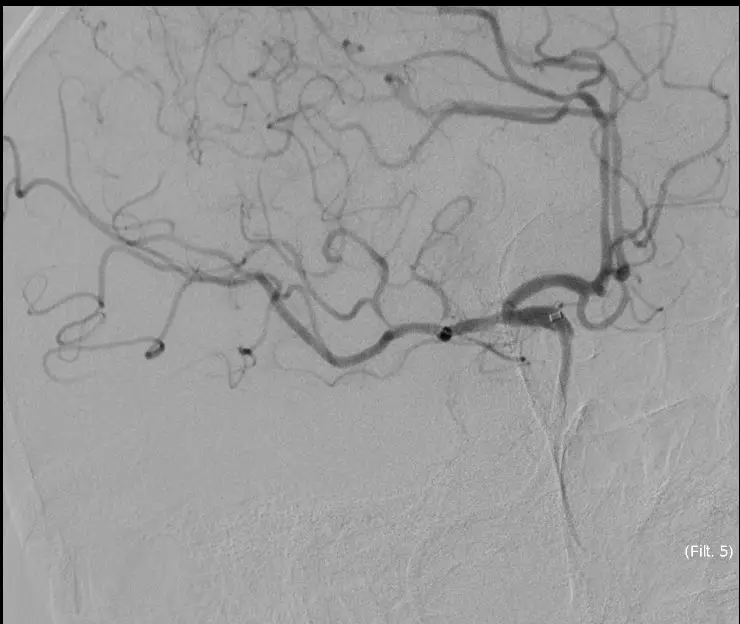

5MIN后

5MIN后

5MIN后

5MIN后

10MIN后

5MIN后

再次观察10MIN后